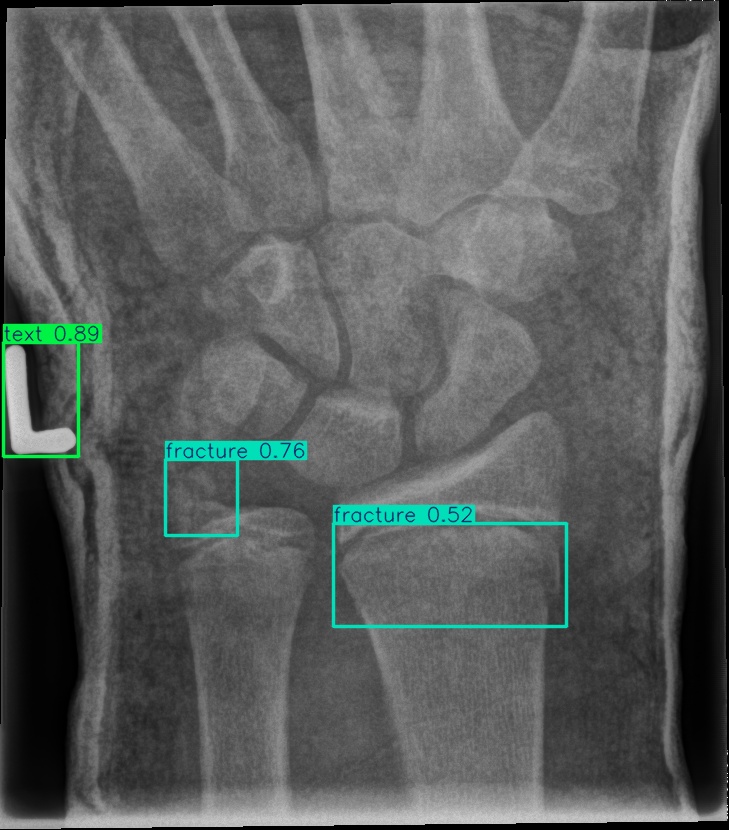

For our experiments, we selected the GRAZPEDWRI-DX images with bounding box annotations in YOLO format, which contains nine classes. Following the data division and augmentation approach outlined by [10], the dataset was randomly divided into 70%70\% training (14,23414,234 images), 20%20\% validation (4,0654,065 images), and 10%10\% testing (2,0282,028 images) sets. To further augment the training data, the number of images in the training set was doubled by adjusting the contrast and luminance of the images. The label distribution and bounding box statistics are shown in Figure 3. Examples of two training images with bounding box annotations from the GRAZPEDWRI-DX dataset are shown in Figure 4.

Refer to caption

Figure 4: Bounding box-annotated X-ray images of pediatric wrist trauma from the GRAZPEDWRI-DX dataset [8].

Figure 8: Sample of five images from the GRAZPEDWRI-DX test set, displaying ground-truth and predicted bounding box annotations: (a-e): ground-truth annotations, (f-j): YOLOv11l annotations, and (k-o): G-YOLOv11 annotations.

Table 4: Confidence scores predicted by YOLOv11l and the proposed G-YOLOv11l detectors for five images from the GRAZPEDWRI-DX test set, PR: pronator sign, FP: False positive.

8(d) fracture, fracture, text 0.770.77, 0.700.70, 0.880.88 0.760.76, 0.520.52, 0.890.89

The results in Table 4, derived from Figure 8, compares the confidence scores predicted by YOLOv11l and G-YOLOv11l detectors for five test images from the GRAZPEDWRI-DX dataset. Figure 8 contrasts ground-truth annotations with predictions from YOLOv11l and G-YOLOv11l. G-YOLOv11l shows slight improvements, such as higher confidence scores for "fracture" and "metal" in Figure 8(a) (0.700.70 and 0.890.89 vs. 0.670.67 and 0.860.86) and for "text" in Figure 8(b) (0.730.73 vs. 0.710.71). However, limitations include false positives, such as for "pronator sign" in Figure 8(c) (score 0.440.44), and lower confidence for some instances, as seen in Figures 8(d) and 8(e). While G-YOLOv11l demonstrates competitive performance, further refinements are required to improve its robustness.